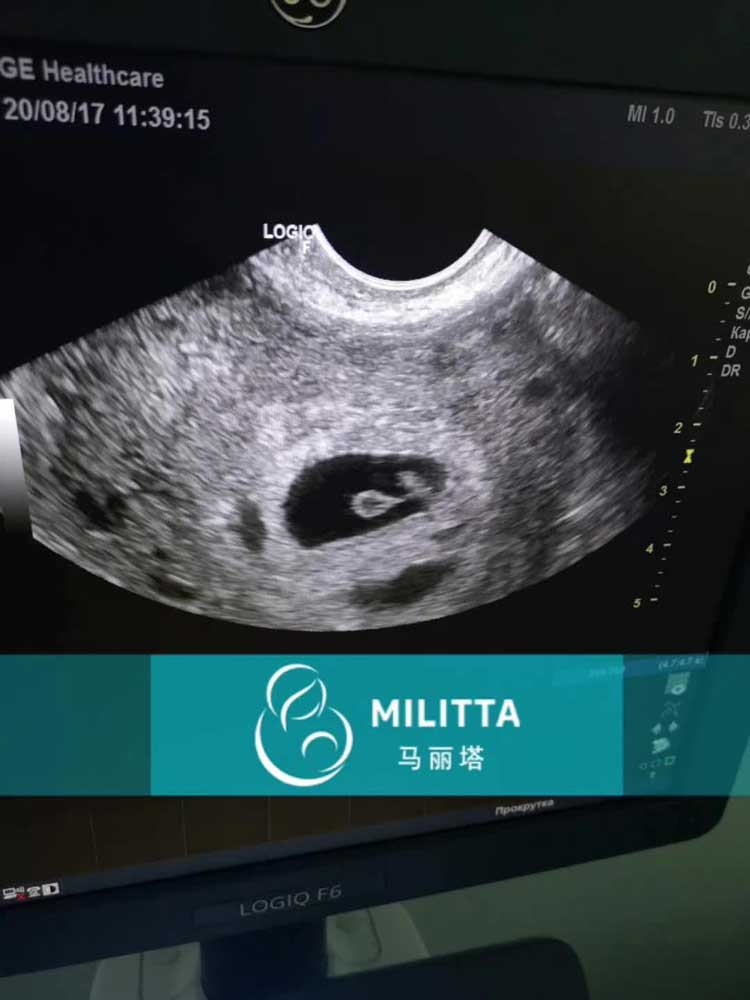

上午陪六个乌克兰妇产医院产检,一对一跟随,很快就完事了,这要是在国内,孕妇产检这挂号排队都会让人烦透。